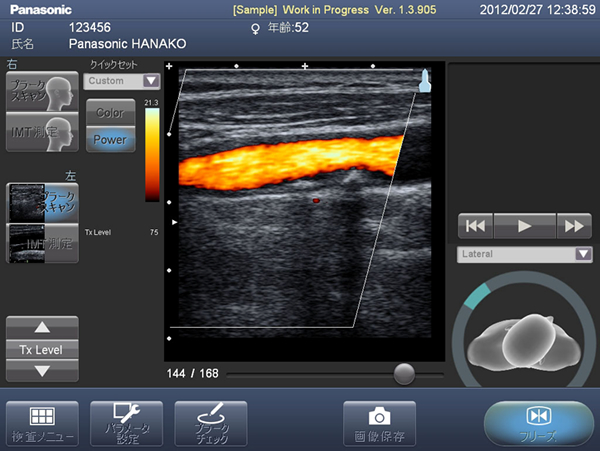

2. カラードプラ機能の搭載によりプラークをわかりやすく描写

血流をカラーで表示することで、プラークの目視診断の精度が向上します。

画面イメージ(カラードプラと日本語表示)